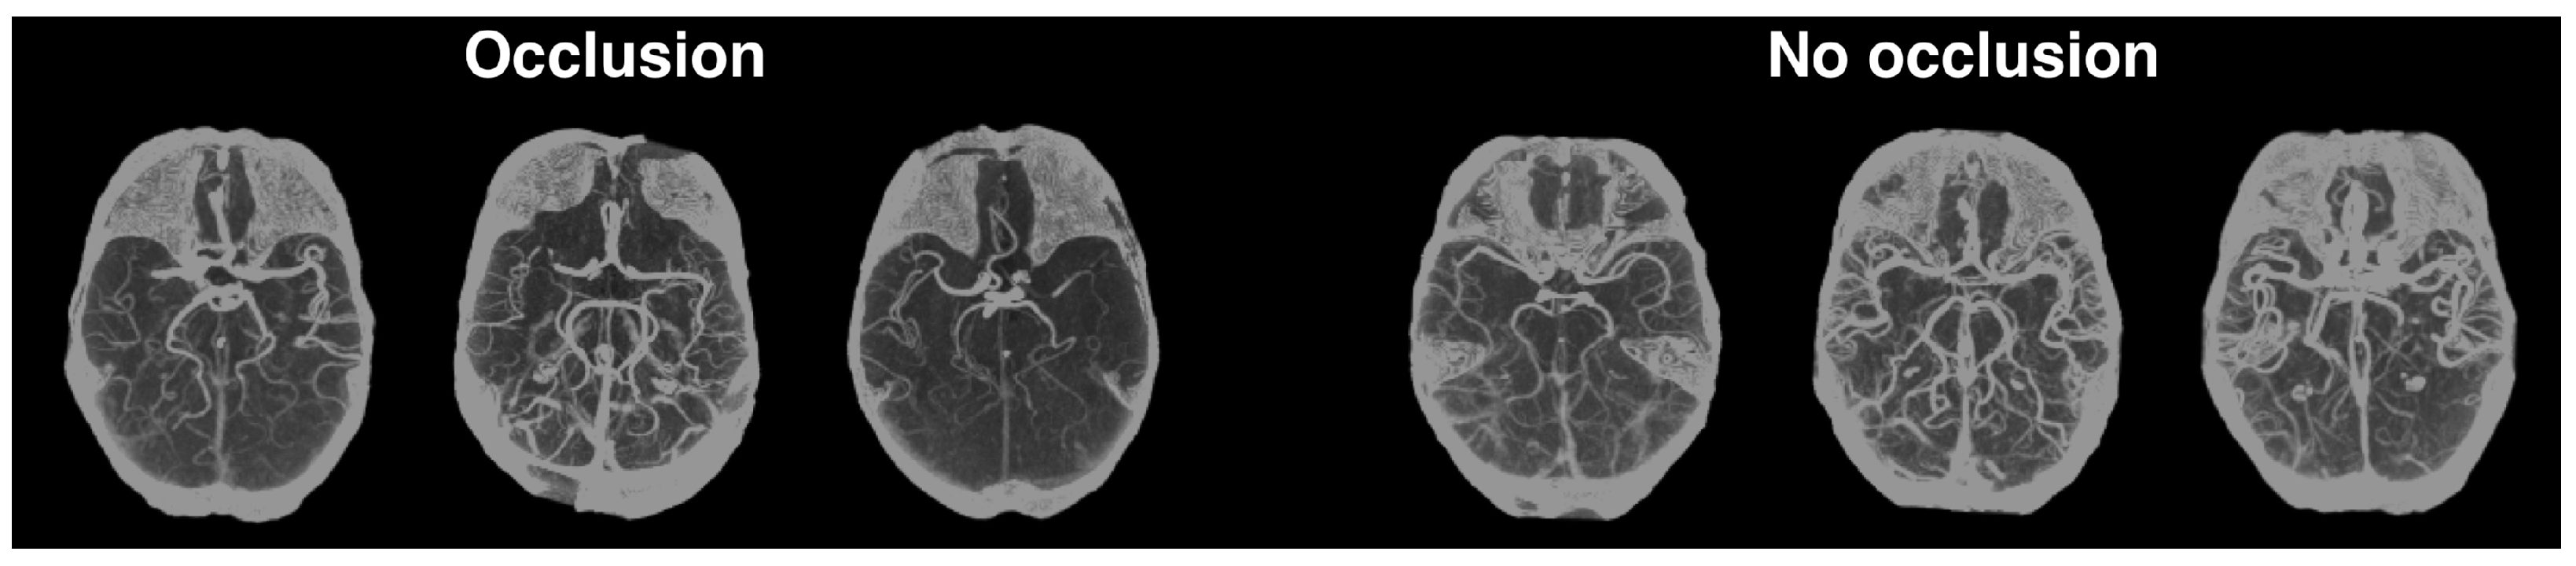

3.3.2.1. Occlusion Prediction

Occlusion Prediction